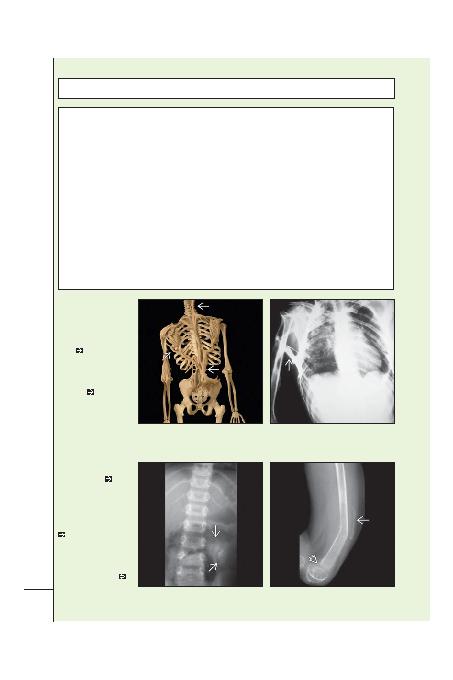

(Sol) Posterior grafi

fibrodisplazi osifikas

progresifayi (FOP)

göstermekte. Kostalar arasini,

omurga boyunca, toraksla

humerus ve toraksla pelvis

arasinda köprüleen matür

kemie

dikkat ediniz. (Sa)

AP radyografi kemik yapilar

kemikle giden FOB'yi (a.k.a.

myositis osifikans progresifa)

göstermekte. Bu humerus ve

göüs kafesi

, yani sira

kostalar arasinda da kemik

köprüleme gösteren ileri

bir olgu. Sonuç tam hareket

kaybidir.

(Sol) AP radyografi sirt

yumuak dokularinda

matür kemiklemeyi

ortaya koymakta. Benzer

kemikleme ön uylukta

mevcuttu. Bu çocuk FOP'un

erken iaretlerini göstermekte.

(Sa) Ayni olgunun lateral

radyografisi ön uyluktaki

kemiklemeyi göstermekte

. Hasta distrofik kemiin

rezorbsiyonu için elatlarla

tedavi edilmiti. Ne yazik ki

heterotopik kemik rezorbe

olmadi, fakat rezorbsiyon

büyüme plainda raitizm

benzeri bulgular oluturdu

.